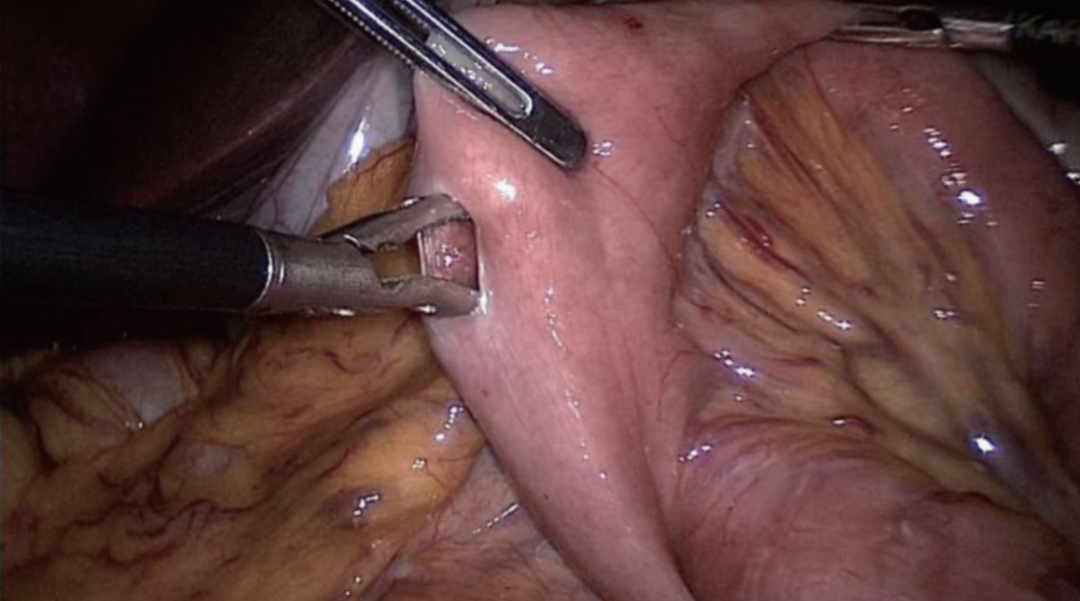

步骤二:FETE吻合

切开食管残端左侧角(图20),将直线吻合器钉仓臂插入远端空肠断端对系膜缘小口(图21),并在胃管引导下将抵钉臂插入食管残端左侧角开口(图22),行食管-空肠逆蠕动侧侧吻合,即功能性端端吻合(FETE吻合),用直线切割吻合器关闭共同开口(图23)。FETE吻合要求共同开口的关闭方向与食管空肠的切割闭合线或空肠长轴垂直,以预防出现吻合口狭窄。为了更好关闭共同开口,预缝共同开口3针作牵引(图24)。

图21 远端空肠残端插入吻合器钉仓臂